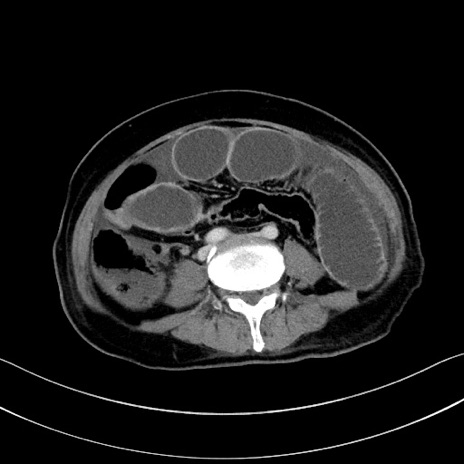

症例28(横断像)

【症例】60歳代男性

【主訴】嘔吐

【現病歴】胃癌にて胃全摘後。食思不振が悪化し、夜中に嘔吐することがある。

【既往歴】胃癌、胃全摘、脾摘、胆摘後

【データ】WBC 5900、CRP 10.56